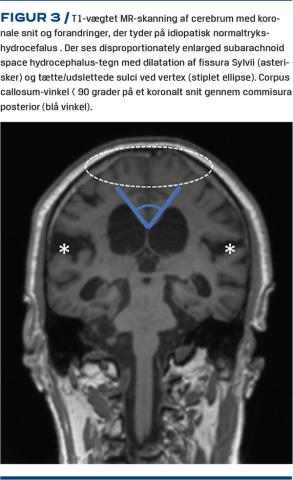

Flere studier har vist, at særlige MR-skanningskendetegn kan bruges til forudsigelse af respons på VPS. En spids corpus callosum-vinkel og tilstedeværelse af såkaldte disproportionately enlarged subarachnoid space hydrocephalus (DESH)-tegn (Figur 3) ser ud til at have størst prognostisk værdi [8, 21]. Tilstedeværelsen af DESH opfattes af mange som central ved iNPH, og en subklassificering i DESH og non-DESH er blevet foreslået [22].